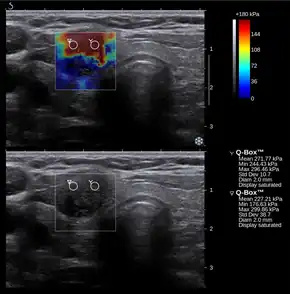

Elastography

Nowadays, the medical imaging modality of elastography can also be used to determine the stiffness of tissues. Manual palpation has several important limitations: it is limited to tissues accessible to the physician's hand, it is distorted by any intervening tissue, and it is qualitative but not quantitative. Elastography is able to overcome many these challenges and improve on the benefits of palpation.

Elastography is a relatively new technology and entered the clinic primarily in the last decade. The most prominent techniques use ultrasound or magnetic resonance imaging (MRI) to make both the stiffness map and an anatomical image for comparison.